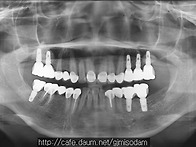

이수행 12.09.06안녕하세요. 공주 미소담 치과 보철과 김계순 원장입니다. 앞니의 ..